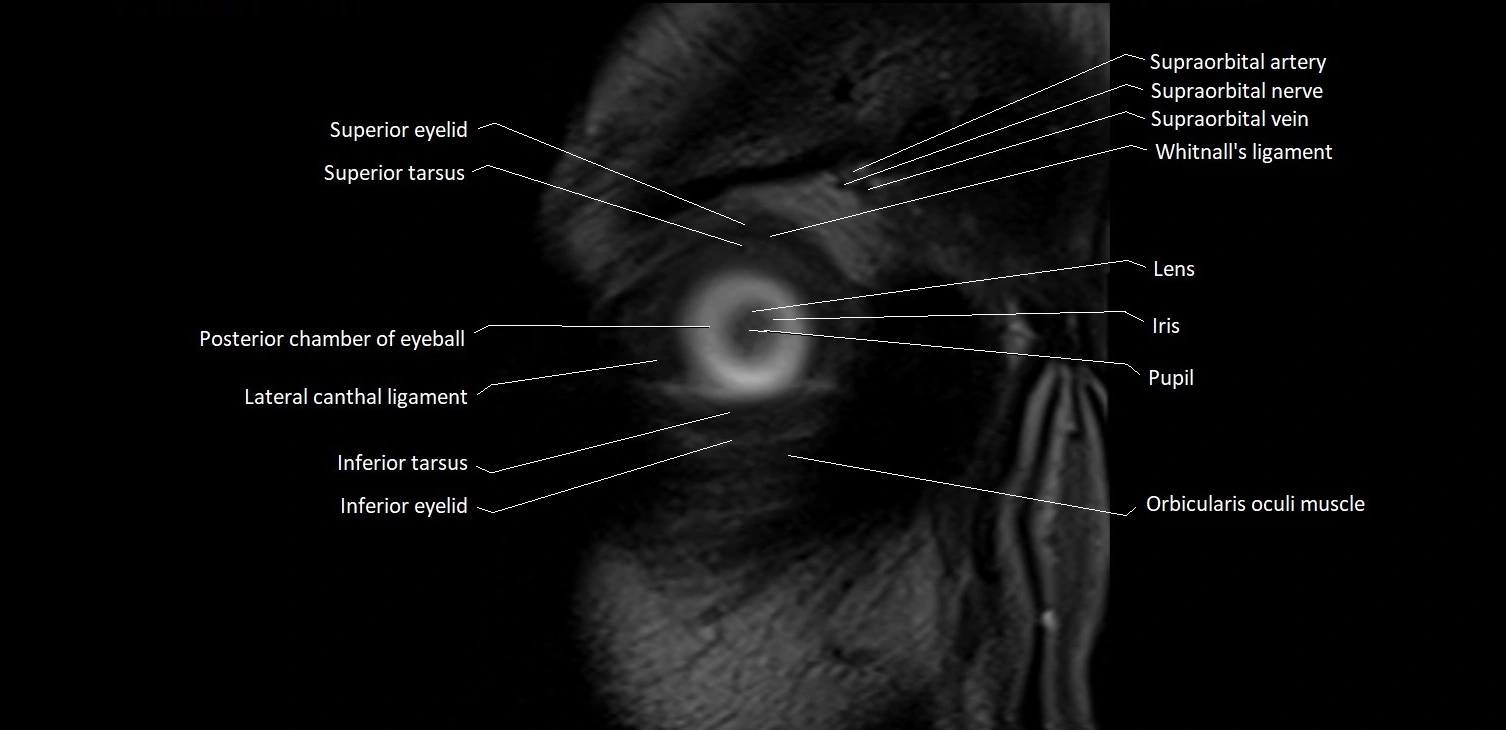

- Superior eyelid

- Superior tarsus

- Inferior eyelid

- Inferior tarsus

- Posterior chamber of eyeball

- Pupil

- Iris

- lens of the eye

- Lateral canthal ligament

- Orbicularis oculi muscle

- Whitnall's ligament

- Supraorbital artery

- Supraorbital nerve

- Supraorbital vein

- Supratrochlear artery